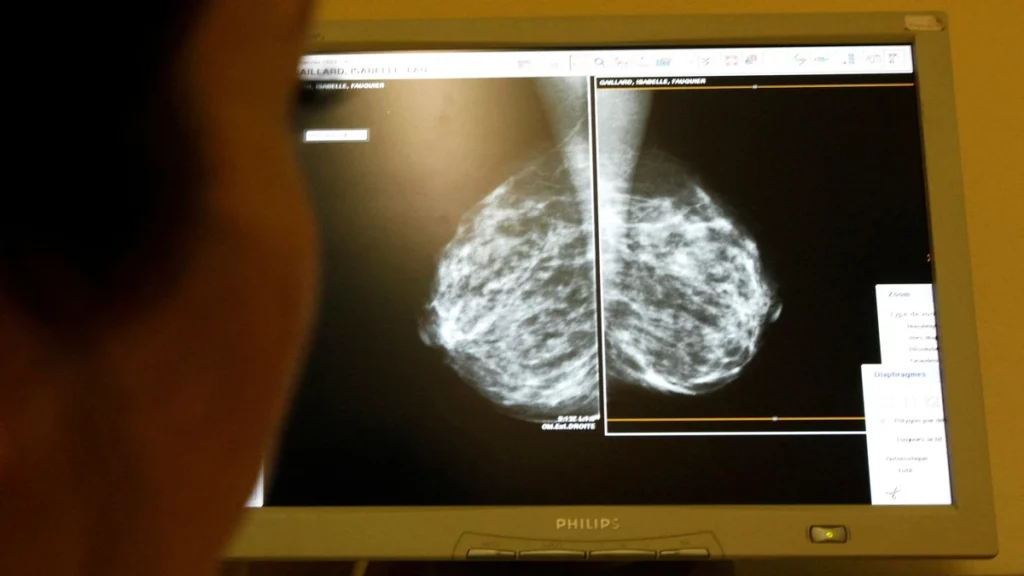

Research and treatment protocols for cancer have gained pace in the last decade. Proper arrangements of cancer research and holding clinical trials are vital to increasing the understanding of how to treat or prevent cancer. Developing new techniques, including using magnetic bacteria for early detection, diagnosing, and treating diseases, and improving support and care services for cancer […]